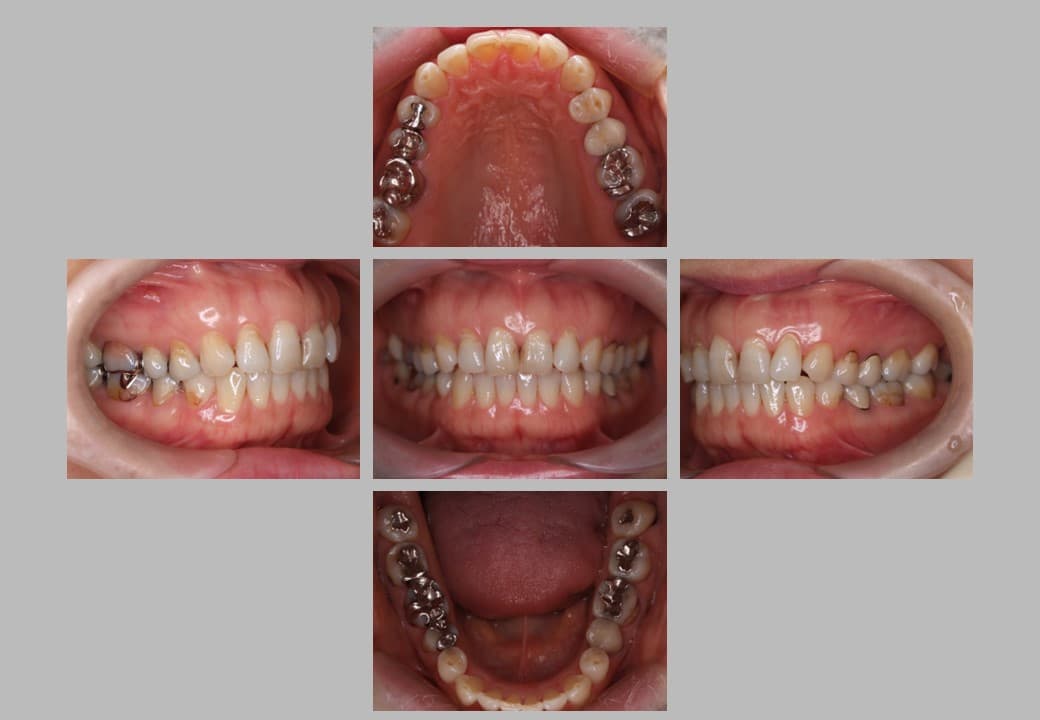

セラミック治療 (メタルフリー治療)の症例紹介①

治療希望:金属の詰め物が取れたセラミックの治療希望

治療内容:根管治療+セラミック治療

治療期間:約6ヶ月

治療前

根管治療+セラミック治療の実施事例です。